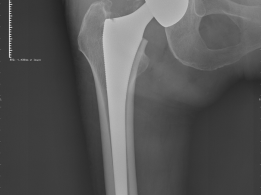

加速康复外科理念让高龄髋关节置换术患者喜开颜

近日我院骨伤科在高龄患者髋关节置换术围手术期运用加速康复外科理念,综合麻醉镇痛、微创...

特殊体位下闭合复位微创治疗高龄股骨粗隆间骨折

近日,我院骨伤科顺利为一名83岁高龄的股骨粗隆间骨折患者完成手术。该患者因摔倒致左...